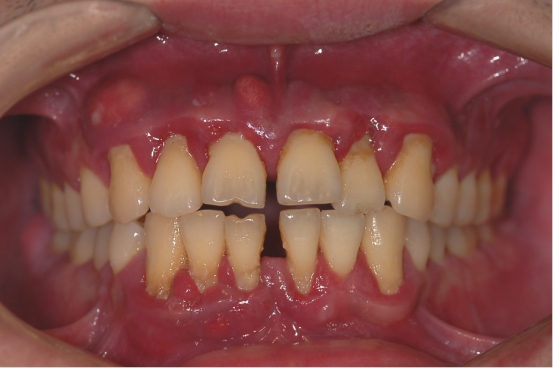

牙龈萎缩及牙齿敏感

当我们的牙槽骨萎缩时,牙龈会跟着萎缩,牙龈萎缩会导致牙根暴露,继而出现牙齿敏感。

牙缝越来越大,牙齿移位,最后脱落

有的患者发现随着年龄的增长,门牙,尤其是上门牙的牙缝越来越大,牙齿逐渐散开。这是因为我们牙齿的“土壤”即牙槽骨高度越来越低,不足以支撑我们的牙齿,牙齿在很轻的力量的长期作用下,比如说话时舌头作用于牙齿的力就会造成牙齿的移位,导致牙缝越来越大。